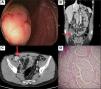

Se abordó por diarrea crónica, se solicitaron estudios en sangre y heces (tabla 1). La esofagogastroduodenoscopia se encontró dentro de los parámetros normales; el reporte histopatológico informó de gastropatía congestiva no atrófica, sin atrofia de vellosidades en el duodeno y en la colonoscopia se observó una lesión exofítica de 30mm en el ciego, de superficie ulcerada y friable a la manipulación (fig. 1A). En la tomografía abdominopélvica contrastada se observó una lesión sobre el borde medial e inferior del ciego, con engrosamiento focal de 18mm de espesor, necrosis e imágenes ganglionares a nivel paracecal (figs. 1 B y C).

A. Colonoscopia que evidencia una lesión de 3cm en el ciego. B. y C. TAC con contraste en corte coronal y axial, que pone de manifiesto una lesión en el borde medial e inferior del ciego, caracterizada por un engrosamiento focal de la pared de aproximadamente 18mm de espesor con extensión endoluminal. D. Corte histopatológico de un tumor neuroendocrino bien diferenciado grado 2; se observa una neoplasia epitelial que presenta crecimiento en forma de nidos, con células de núcleos moderadamente pleomórficos y cromatina laxa o densa, además de presencia de mitosis y un citoplasma escaso. La neoplasia se desarrolla en un estroma vascularizado y muestra infiltración a través de todas las capas del colon, rebasando la serosa.

Posteriormente fue sometido a hemicolectomía derecha con resección ganglionar, con valores prequirúrgicos de cromogranina A 117ng/ml (VN<85ng/ml) y somatostatina 6ng/ml (VN<10ng/ml) dentro de los parámetros normales. El reporte histopatológico informó de un tumor neuroendocrino bien diferenciado grado 2 (pT2, pN1, pM0), invasión de todas las capas, rebasando la serosa, permeación linfovascular presente, cromogranina positivo: +++; sinaptofisina positivo +++; Ki-67: positivo: 3-20% y metástasis a 2/28 ganglios (fig. 1 D).